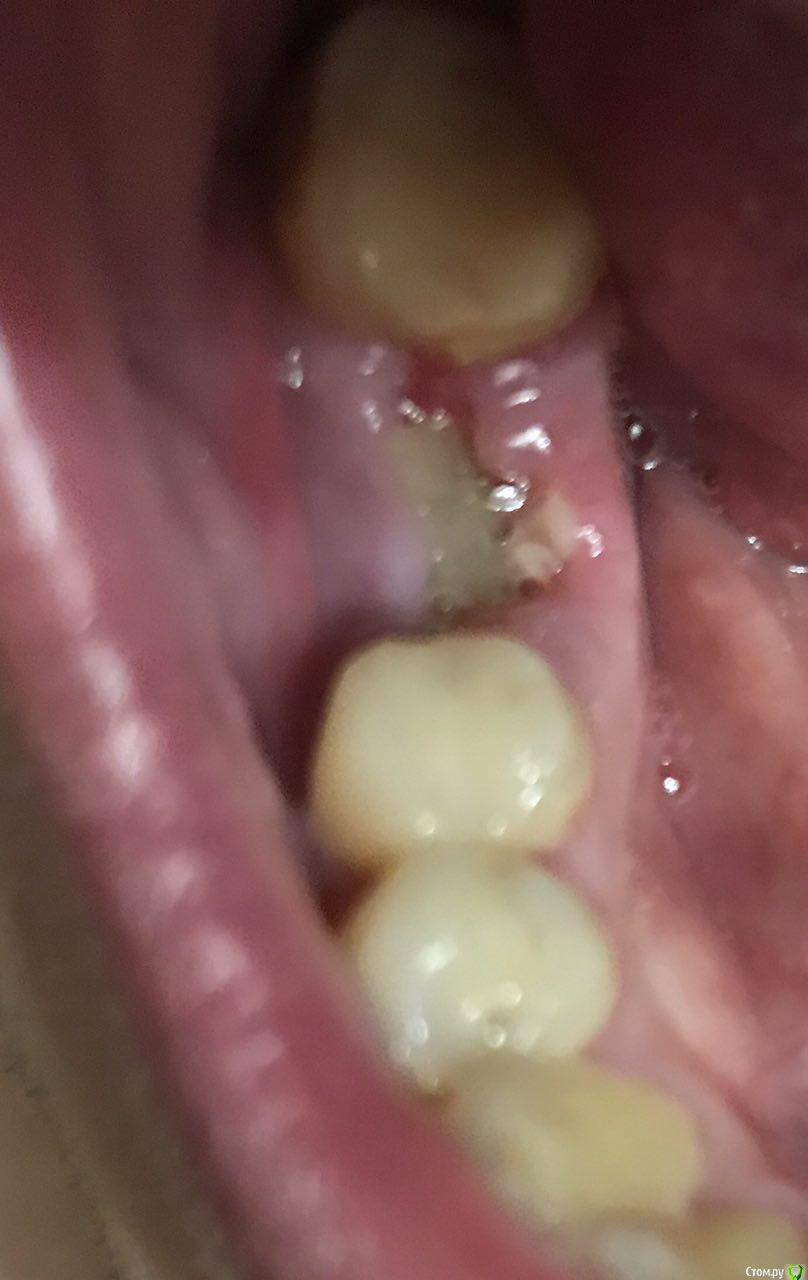

annag Опубликовано 10 сентября, 2017 Поделиться Опубликовано 10 сентября, 2017 Всем добрый день!В субботу 2 сентября удалил нижнюю шестерку, так как была большая киста, планирую поставить имплант.Удаление было сложным, зуб сам по себе большой, пришлось распиливать пополам и удалять частями. Удалили минут 30. В итоге по словам хирурга прошло всё нормально, один корень был с расширением на конце, поэтому так сложно. Положили в лунку какую-то губку, лекарств не назначили, кроме обезболивающих.Дальше с первого дня лунка начала болеть и так болела всю неделю. А мне улетать в понедельник 11.09, поэтому начал напрягаться. Боли слабее не становились, по ночам особенно. Спасался кетановом при сильных болях, пропил 5 дней немисил.Хирург, который удалял, улетел отдыхать, а 8.09 врач терапевт, она тоже присутствовала на удалении, почистила мне лунку. При этом сгусток был на месте, а неприятных запахов из лунки не было, то есть признаков воспаления какого-то. Возможно в зубе была не киста, а гранулирующий процесс она сказала. Но лунку она от этого всего почистила, хотя возможно и не полностью. Плюс выписала антибиотик аугментин 1000 пропить 5 дней.Была надежда что всё пройдет, но нет. 9.09 ночью и утром боли как и раньше, дальше немисил и полдня нормально, немного тянуло, вечером заболело, немисил снова помог. Ночью с 10 на 11 снова заболело, но уже не так сильно, как раньше, но кетанов пришлось выпить, чтобы спать.Врач, которая чистила, сомневается что дальше делать, идти сегодня к хирургу заново чистить, мало ли она что-то не дочистила или ждать, т.к. идёт просто заживление так.Сегодня утром 10.09 тянет немного, но возможно действует еще ночной кетанов, что же делать дальше? Завтра в 9 утра улетаю в отпуск в Тай. Идти сегодня к хирургу или ждать еще и если что идти уже в Тае? (не хотелось бы)Снимок делал, остатков зуба не замечено, фото текущее лунки так же прилагаюЗаранее огромное спасибо за советы! Ссылка на комментарий